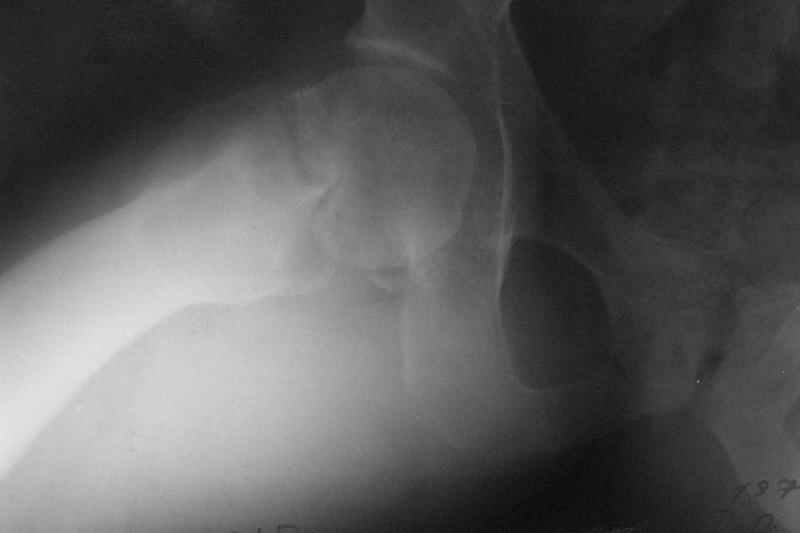

Stephen Kottmeier 17 Октябрь 2005, 21:05

friend

dhs will not correct improper biomechanical environment and may further compromise vascular

integrity consider establish vascular status via mri

and if viable follow with proximal valgus osteotomy

Отправитель: Peter Trafton 17 Октябрь 2005, 21:21

I think that this 31 yo deserves a try with valgus osteotomy, as so nicely illustrated by stephen kottmeier. However, I'd do it no matter what an MRI shows - thus why bother with the MRI? (What sort of data support MRI's ability to predict segmental collapse?)